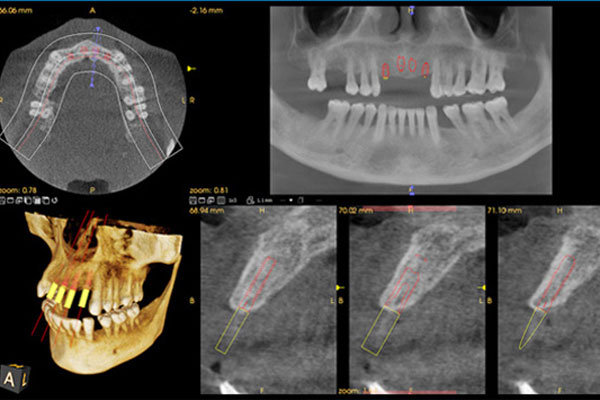

Cone Beam Computed Tomography

CBCT (Cone Beam Computed Tomography) had been introduced in Europe way back in 1996 and in the USA in the early 2000s. It has, since then, been a revolutionary invention that changed the world's dental radiology panorama. In the past couple of years, it has made its advent in the Indian market. With its various benefits for both dentists and patients, CBCT has been quite gripped the diagnostic beat in Kolkata. CBCT has become a part and parcel of dentistry and has thus, significantly improved quality and excellence of dental treatment.